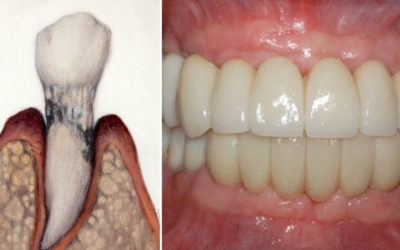

치주질환의 가장 저명한 원인은 치태와 치석입니다. 구강 내 음식물과 세균으로 인해서 치태가 형성되고, 제때 제거되지 못한 치태는 치석을 형성하고 결국 치주질환을 유발해요. 세균들이 잇몸에 염증반응을 유발하는 물질을 분비하고 이로 인해 잇몸이 붓고 잇몸에서 피가나는 증상이 생기는 것으로 보입니다.

잇몸에 발생되는 염증을 ‘치은염’이라고 부르고, 이 경우에 잇몸의 염증치료가 제때 되지 않아 염증이 악화되면 치주염으로 변하게 돼요. 증상이 악화되면 ‘치아상실’까지 초래할 수 있기 때문에 평소 잇몸관리는 필수입니다.